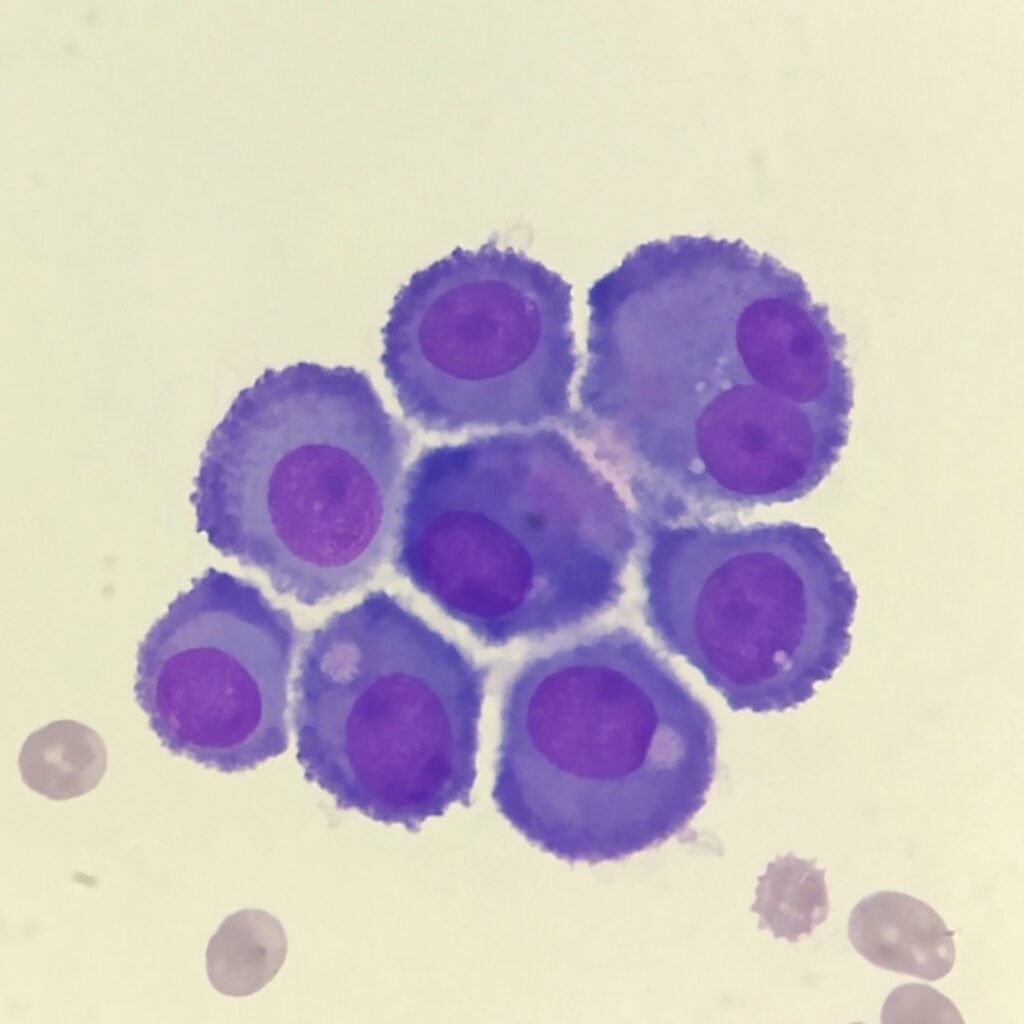

Mesothelial cells are described as having a “fried egg” appearance. They have a round to oval nucleus with smooth borders and evenly distributed chromatin. Nucleloli are usually present. Mesothelial cells may also be multinucleated.

Cells may be seen in clumps, but “windows” between cells still allows for individual counting.